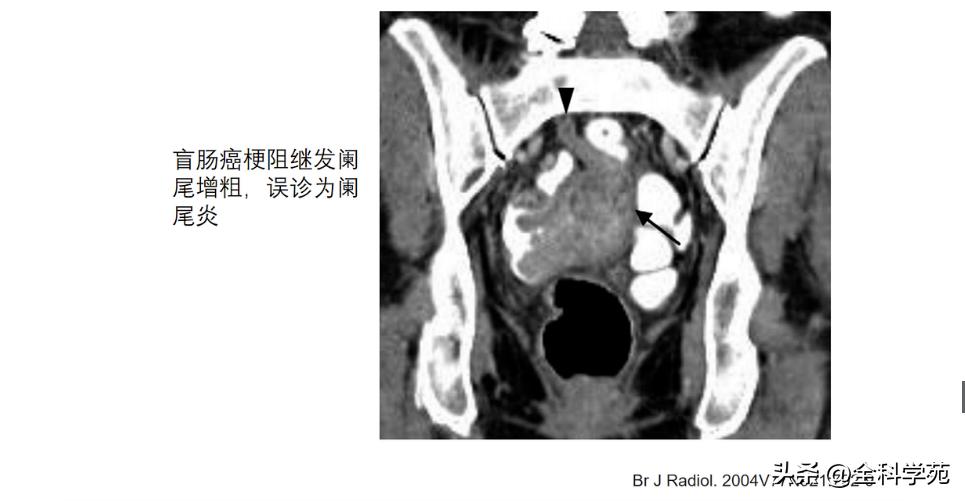

◆ 穿孔 (Perforation)

◆ 局部低强化是穿孔征象